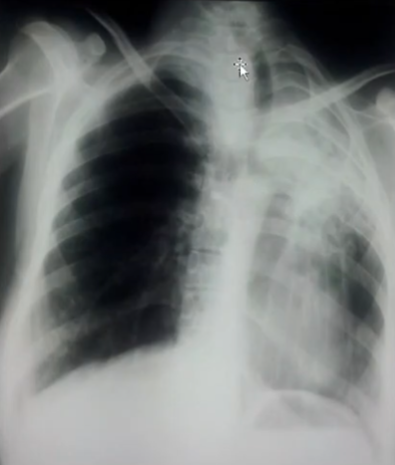

Rx toracică, incidență P-A

DESCRIERE:

la niv. întregului hemitorace stg → opacitate extinsă, nesistematizată, de intensitate mare, omogenă

caracter retractil → tracționează traheea și mediastinul de partea afectată

fără bronhogramă aerică

duce la micșorarea spațiilor intercostale

la niv. hemitoracelui controlateral → hipertransparență compensatorie

DX: atelectazie prin NBP central endobronșic (pe bronhia principală stg)

DD: pleurezie masivă → caracter expansiv